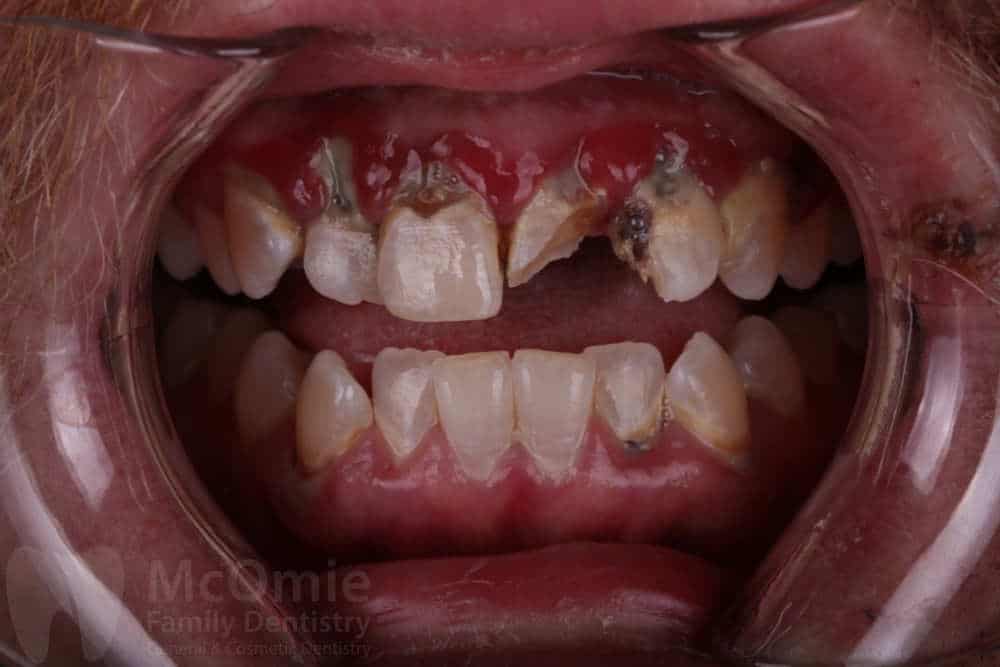

This patient came to us after a traumatic facial injury that left several front teeth fractured and caused severe damage to the surrounding gum tissue. Initial photos show broken teeth and torn soft tissue resulting from the accident. Treatment began with gum surgery and supportive therapy to stabilize and promote healing. Once the tissue improved, crowns were placed on the front four teeth to restore strength, appearance, and function. The result is a smile that looks natural and healthy, with both teeth and gums healing beautifully just two weeks post-op.